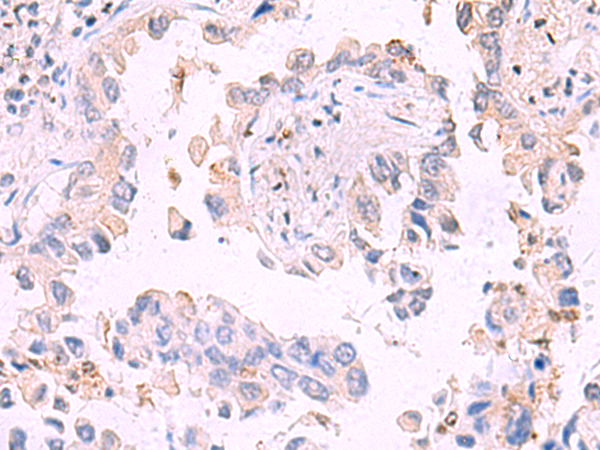

| IHC | 1/30-1/150 | Human,Mouse,Rat |

**摘要**: 报道了一种新型抗人IRGC单克隆抗体的开发,验证了其在肿瘤组织中的特异性结合能力,提示IRGC可能作为癌症诊断的潜在生物标志物。